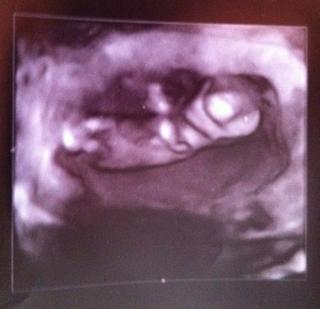

@lu2112 ahoj, zas sa hlasim, tak dnes sme boli na scan - NT screening vsetko ok, krasny je drobec, vsetko tak ako ma byt, srdiecko bije. Ked sa dostanem k scaneru alebo normalnemu fotaku dam foto. Inak sa na vas dotahujeme 😀 podla velkosti sme uz 12tt+5, termin mame 12.10...Akurat ze uz by som mala mat prilepenu placentu a nemam, takze som dostala prikaz najblizsie 2 tyzdne lezat a nechat sa obskakovat, takze v podstate mame uz aj po dovolenke 🙂 este ze som stihla nakupit vsetko podstatne.

@lu2112 Ja som pravidelne vstavala o 5:30 do prace 😖 , to je strasne hlavne v zime sa vykopnut z teplej postielky a hlavne ked tam spokojne spi muz a pes. Ten sa samozrejme hned prestahuje od noh na moje vyhriate miesto 🙂 . Takze teraz si to uzivam,ze ziadne vstavanie, ale cakala som,ze budem dlhsie spavat,len maly a hlad ma zobudia. Dnes rano stikutal, chudatko a dlho. Drzim palce na scane zajtra, ak je to prvy,tak to je zazitok. Hlavne srdiecko ako rychlo a silno bije. Ja som bola prekvapena, ze maly vyzeral ako hotovy cloviecik. Ja som cakala este take nedokonale tvary a ten nas si este aj kychol 😀. Potom napis info

Tak uspesne hlasim prichod no Croydon Hospital ako ze dobre ale som rada ze tu nemusim rodit nebolo mi to tam vobec sympaticke 😒 ale male vyzera v poriadku len sa stale otacala chrptom takze sme ho ani z predu nevideli aj fotka je odchrbatika no asi sme ho zobudili lebo naj prv sa nehybalo a potom sa uz len skrivalo 😀. Dala som si spravit testy na Down syndrom ak sa neozvu do buduceho tyzdna znamena ze vsetko je v norme 😅 Dalsi scane mame 25.05 a consultanta musim videit 31.05 kvoli rodinej anamneze 😉. Inak mam nizko placentu tak povedali ze mozem obcas krvacat ale ze vzdy mame doist do nemocnice lebo pricini mozu bit aj ine 😅 ale tesim sa velmi

@radusiq super ze scan dopadol dobre a nebojkaj vsetko bude ok s placentou hlavne oddychuj a uzivaj si dovolenku a drobcek je nadherny 🙂

@cimage tak gratulujem si sikovna pekne v case si to stihla ja ako sa poznam sa budem balit z porodnymi bolestami 😀 Uz pocitas dni ja mam v stvrtok scane tak sa tesim ze uvidime nase zlato male aleked si predstavim ze este kolko mame pred sebou tak dlhu cestu mame este 😅 ale vsetci tvrdia ze to rychlo ubehne tak im budem verit 😀